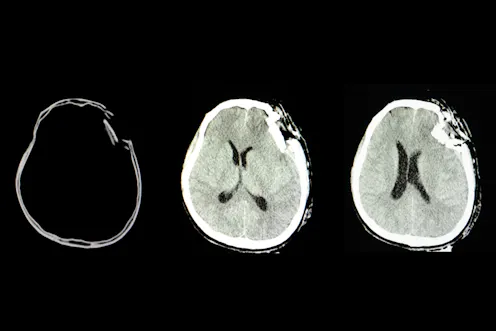

People with traumatic brain injuries are more likely to be violent, more likely to go to prison at a younger age (and have multiple convictions) and more likely to disobey prison rules. They are also more likely to abuse alcohol and drugs, more likely to have mental health problems and more likely to attempt suicide. Surprisingly, given the vast range of negative outcomes for this type of trauma, there have been few studies on brain injury among female prisoners.

Most people in prison are men and most of what we know about brain injury among prison populations is based on men, such as the cause (commonly through fights) and the impact on brain functioning following injury. But female inmates have higher rates of repeated brain trauma than men, often as a result of being victims of partner violence.

The different ways that men and women receive brain injuries might mean that the injury impact differs, but we don’t know enough about this yet. In one study, women reported frequent problems with anxiety, depression and sleep, whereas men complained of problems with concentration and feeling irritated or annoyed. This suggests that the focus of rehabilitation and skills development following traumatic brain injury, may need to be different for men and women.